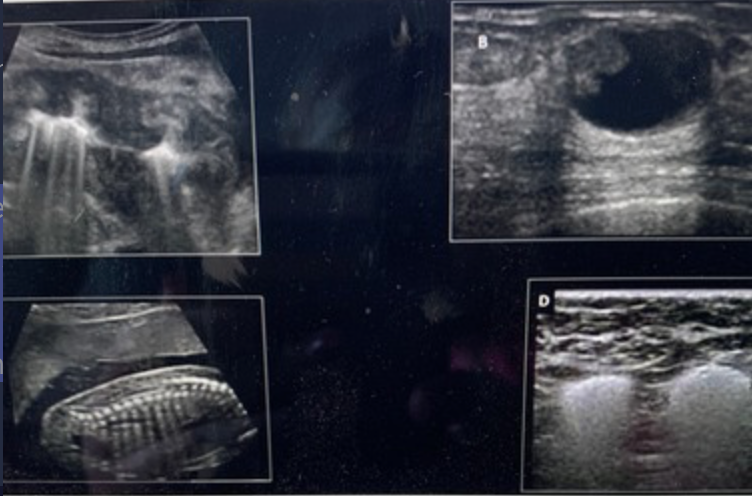

Which image demonstrates refractive shadowing?Use your mouse to position the cursor over the image and click to set your answer.

a. top left

b. top right

c. bottom left

d. bottom right

bottom right

Which image demonstrates posterior enhancement? Use your mouse to position the cursor over the image and click to set your answer.

top right